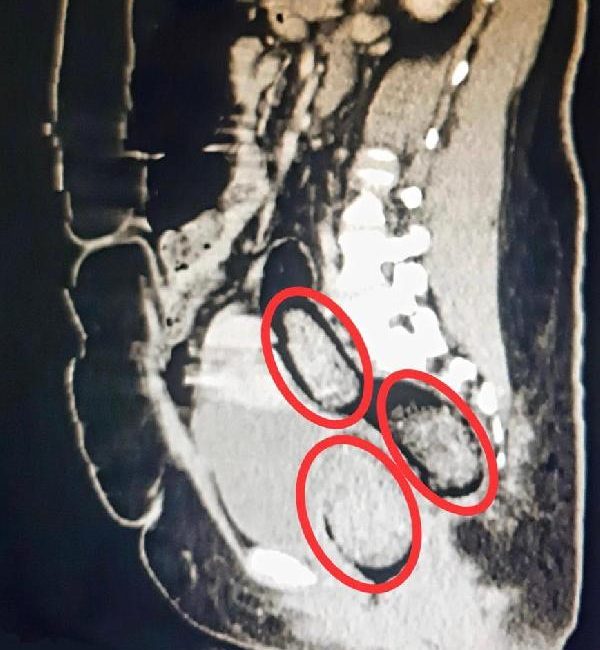

Volkan KARABAĞ/KARS, (DHA)- KARS’ta, polisin durdurduğu yolcu otobüsünde hareketinden şüphelenilen İran uyruklu kadının hastanede çekilen röntgeninde, makatında uyuşturucu tespit edildi. Uyuşturucu cerrahi operasyonla çıkarılırken, şüpheli tutuklandı.

Kars Emniyet Müdürlüğü Narkotik Suçlarla Mücadele Şube Müdürlüğü ekipleri, Digor-Kars kara yolundaki uygulamada, yolcu otobüsünde arama yaptı. Polis, hareketlerinden şüphelendiği İran uyruklu Hadıs Aeınezad’ı (31) gözaltına aldı. Kars Harakani Devlet Hastanesi’ne götürülen Aeınezad’ın çekilen röntgeninde, makatında uyuşturucu tespit edildi. Cerrahi operasyonla kadının makatından 3 parça halinde toplam 318 gram metamfetamin çıkarıldı. Emniyetteki işlemlerinin ardından adliyeye sevk edilen şüpheli, çıkarıldığı hakimlik tarafından tutuklandı. (DHA)